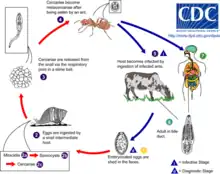

Life cycle

Dicrocoelium dendriticum spends its adult life inside the liver of its host. After mating, the eggs are excreted in the feces.

The first intermediate host, the terrestrial snail (Cochlicopa lubrica in the United States), consumes the feces, and becomes infected by the larval parasites. The larvae (or miracidium) drill through the wall of the gut and settle in its digestive tract, where they develop into a juvenile stage. The snail attempts to defend itself by walling the parasites off in cysts, which it then excretes and leaves behind in the grass or substrate.

The second intermediate host, an ant (Formica fusca in the United States[13]), uses the trail of snail slime as a source of moisture. The ant then swallows a cyst loaded with hundreds of juvenile lancet flukes. The parasites enter the gut and then drift through its body.

Most of the cercariae encyst in the haemocoel of the ant and mature into metacercariae, but one moves to the sub-esophageal ganglion (a cluster of nerve cells underneath the esophagus). There, the fluke takes control of the ant's actions by manipulating these nerves.[14] As evening approaches and the air cools, the infected ant is drawn away from other members of the colony and upward to the top of a blade of grass. Once there, it clamps its mandibles onto the top of the blade and stays there until dawn. Afterward, it goes back to its normal activity at the ant colony. If the host ant were to be subjected to the heat of the direct sun, it would die along with the parasite.

Night after night, the ant goes back to the top of a blade of grass until a grazing animal comes along and eats the blade, ingesting the ant along with it, thus putting lancet flukes back inside their host. They live out their adult lives inside the animal, reproducing so that the cycle begins again.[15][16][17] Infected ants may contain 100 metacercariae, and a high percentage of ants may be infected. Typical infections in cattle may be in the tens of thousands of adult worms.[18]